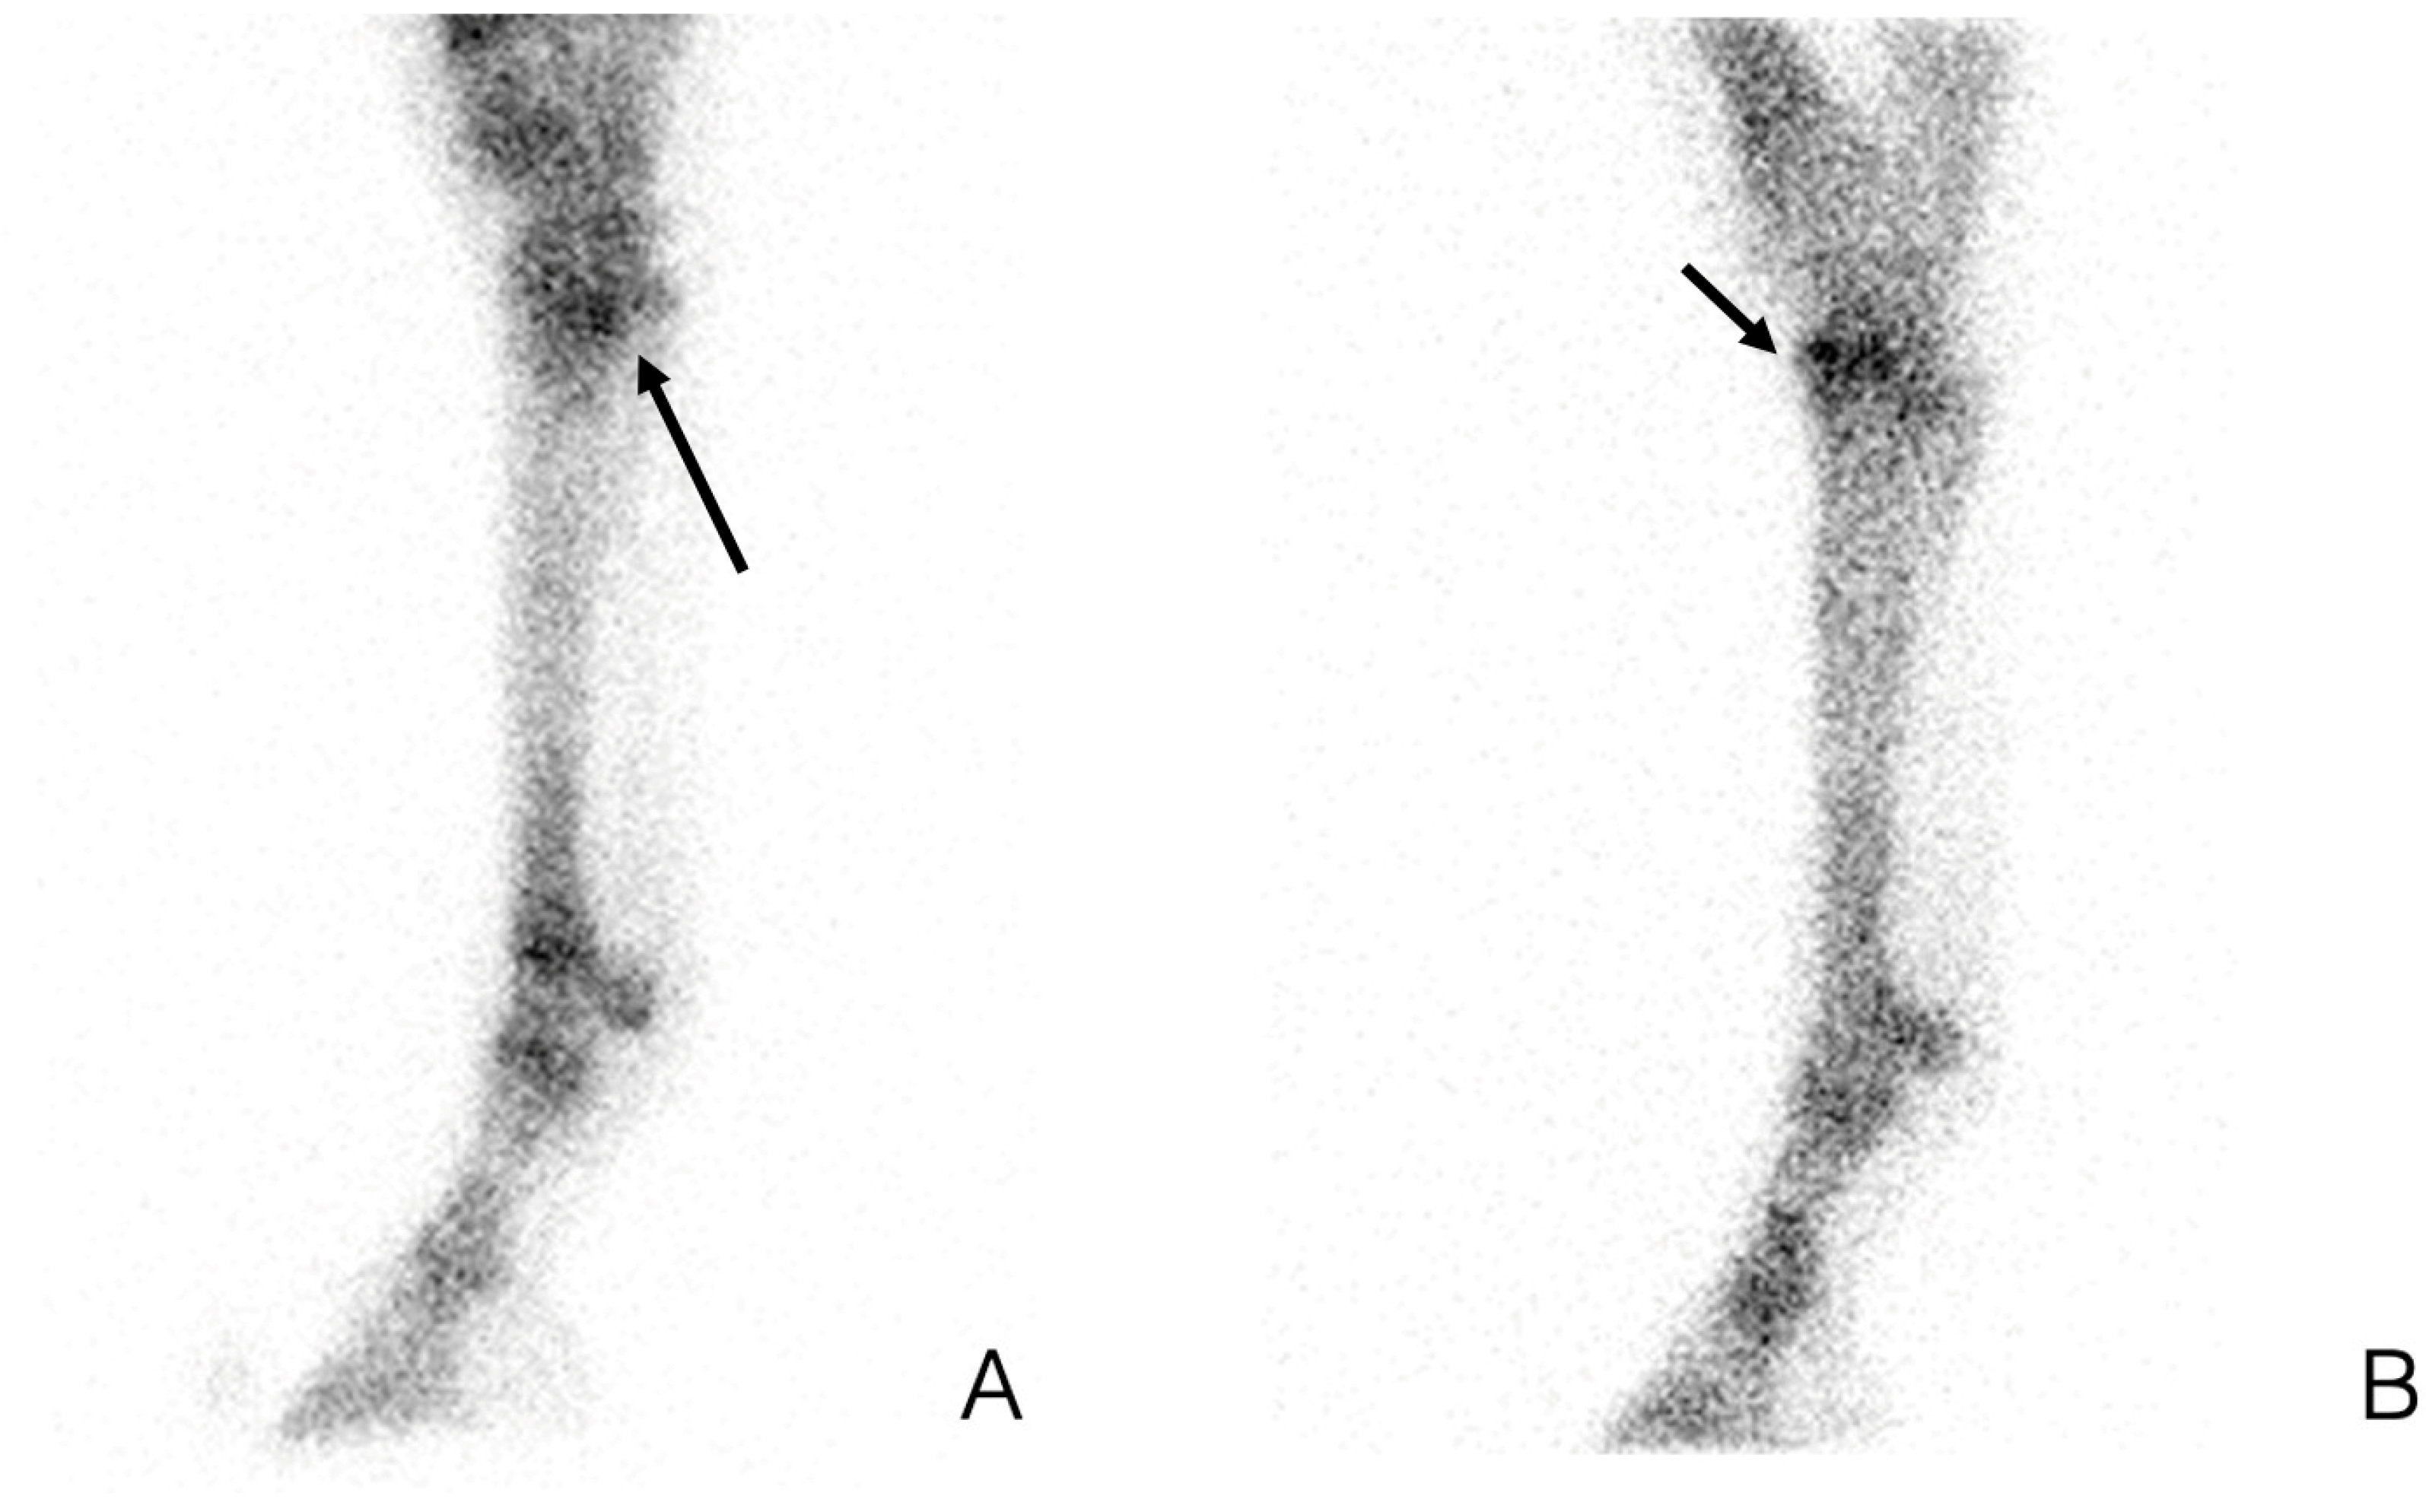

2.1. Imaging of a Focal Area When Pain Has Been Localized but Radiographs Do Not Show Any Abnormalities

2.2. Imaging of a Large Area When Lameness Cannot Be Localized with Diagnostic Analgesia

2.3. Whole Body Imaging for Multiple Limb Lameness or Poor Performance